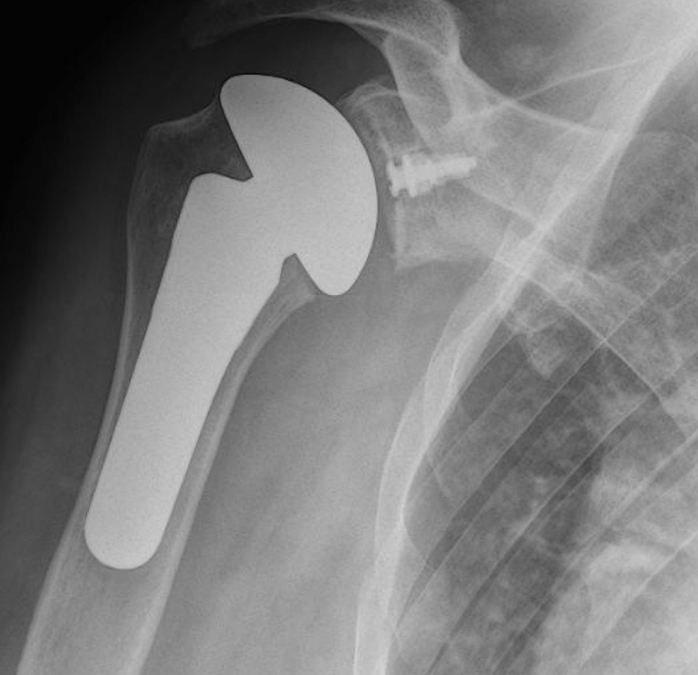

The shoulder is a ball and socket joint. It consists of a round head of the upper arm bone called the humeral head. This ball fits into a socket in the shoulder called the glenoid fossa. A total shoulder replacement removes the damaged round head and socket and replaces them with metal and plastic parts, while maintaining their anatomical position.

A partial shoulder replacement involving the replacement of only the ball or the humeral head with a metal ball and stem. This surgery may be recommended when the humeral head is severely damaged but the socket or the glenoid fossa is normal.

A partial shoulder replacement involving the replacement of only the surface of the ball or the humeral head with an artificial cap without the stem. This is an alternative to the stemmed hemiarthroplasty allowing for more bone preservation.

After surgery, you will recover in the hospital for 1 or more days, depending on your individual health conditions and needs. An X-ray will be obtained and your shoulder will be immobilised in a sling. Physiotherapy rehabilitation will begin almost immediately following the surgical procedure. The initial goals of treatment are to reduce swelling and pain, while restoring passive motion. Subsequently, the treatment goals shift to active motion, strengthening the shoulder and increased functionality of the affected arm. A tailored, well planned rehabilitation program is essential for the success of a shoulder replacement in the hospital and while recovering at home.

Choosing the right hand therapist starts with them being able to read your X-rays and then fabricate the right brace for you. The therapists at Action Rehab Hand Therapy Clinic are experienced in assessing and reading X-rays.